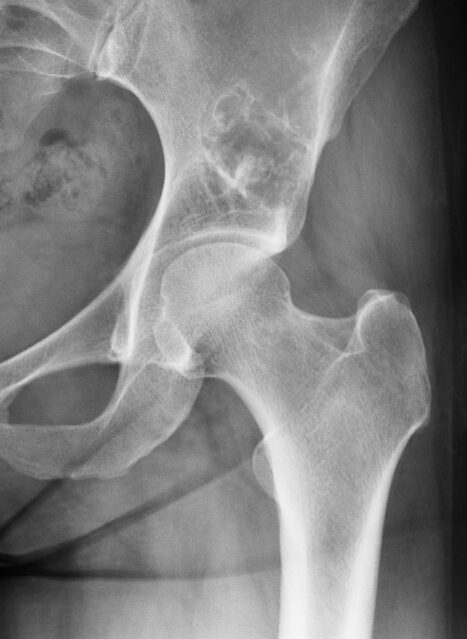

瘤软骨钙化

瘤软骨常表现为环状钙化, 是诊断软骨类肿瘤较为可靠的影像学征象。环状钙化形成于环状软骨、以及软骨小叶边缘的软骨基质。钙质沉着可呈小点状、小条状、半环状或弧形;亦可浓密相连、重叠呈菜花状。钙化环的形态和密度可反映瘤组织分化程度, 通过观察钙化环的形态和密度,有助于良恶肿瘤的鉴别。良性瘤软骨之瘤细胞分化好、生长缓慢、血供充分, 钙化环完整,密度高, 边缘清楚。良性软骨类肿瘤如骨软骨瘤(图 35)、软骨母细胞瘤(图 36)、内生软骨瘤(图 37)等均可于瘤组织内发生环形钙化。恶性瘤软骨则呈密度淡薄, 边缘模糊的不规则钙化,恶性骨肿瘤的环形钙化,最多见于软骨肉瘤(图 38),其次是骨肉瘤。CT 是发现肿瘤内软骨钙化最为敏感的检查方法。

图 38.瘤软骨钙化:软骨肉瘤